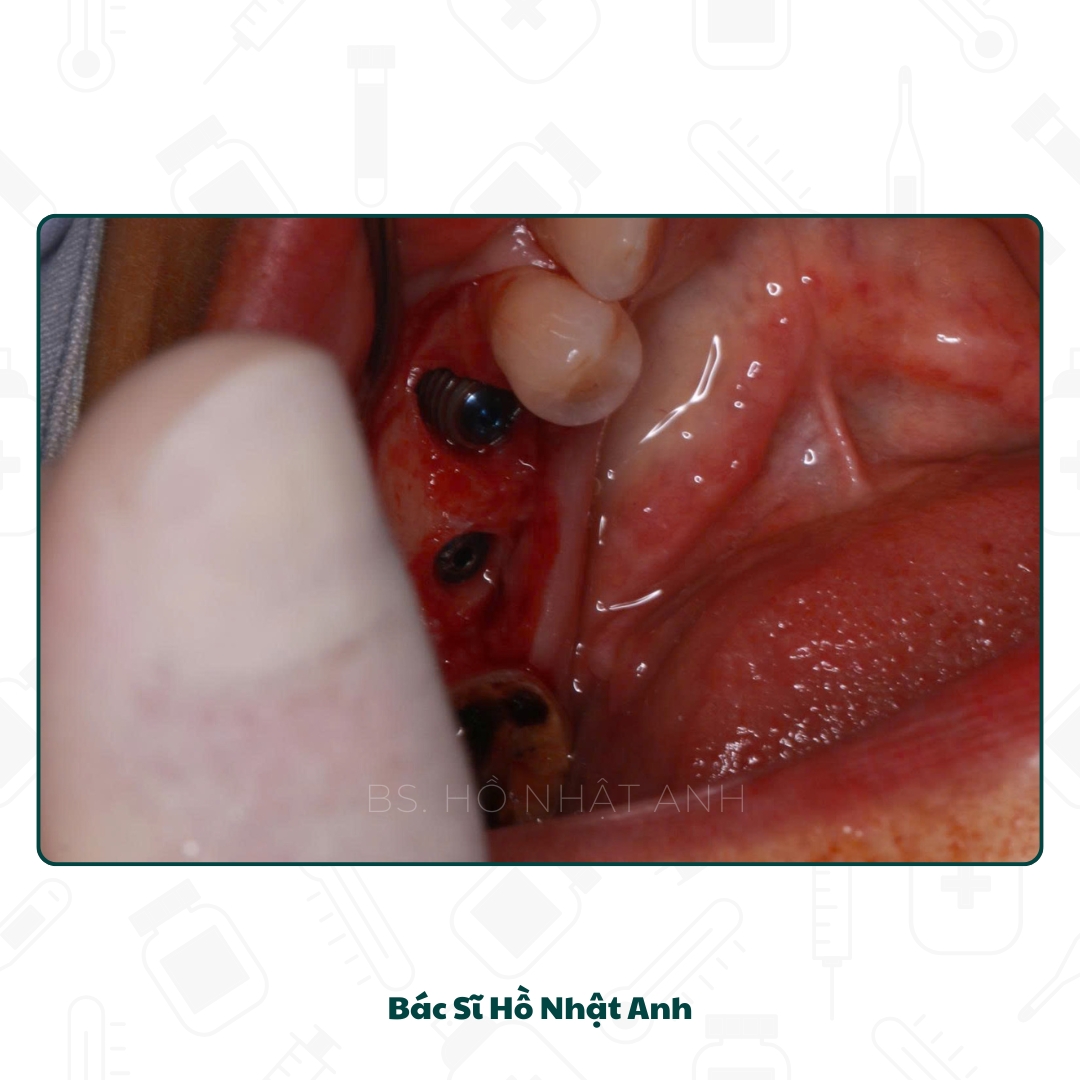

Quy trình cắm Implant, Ghép xương, xử lý mô mềm Và Lắp răng

Quy Trình Cắm Ghép Implant